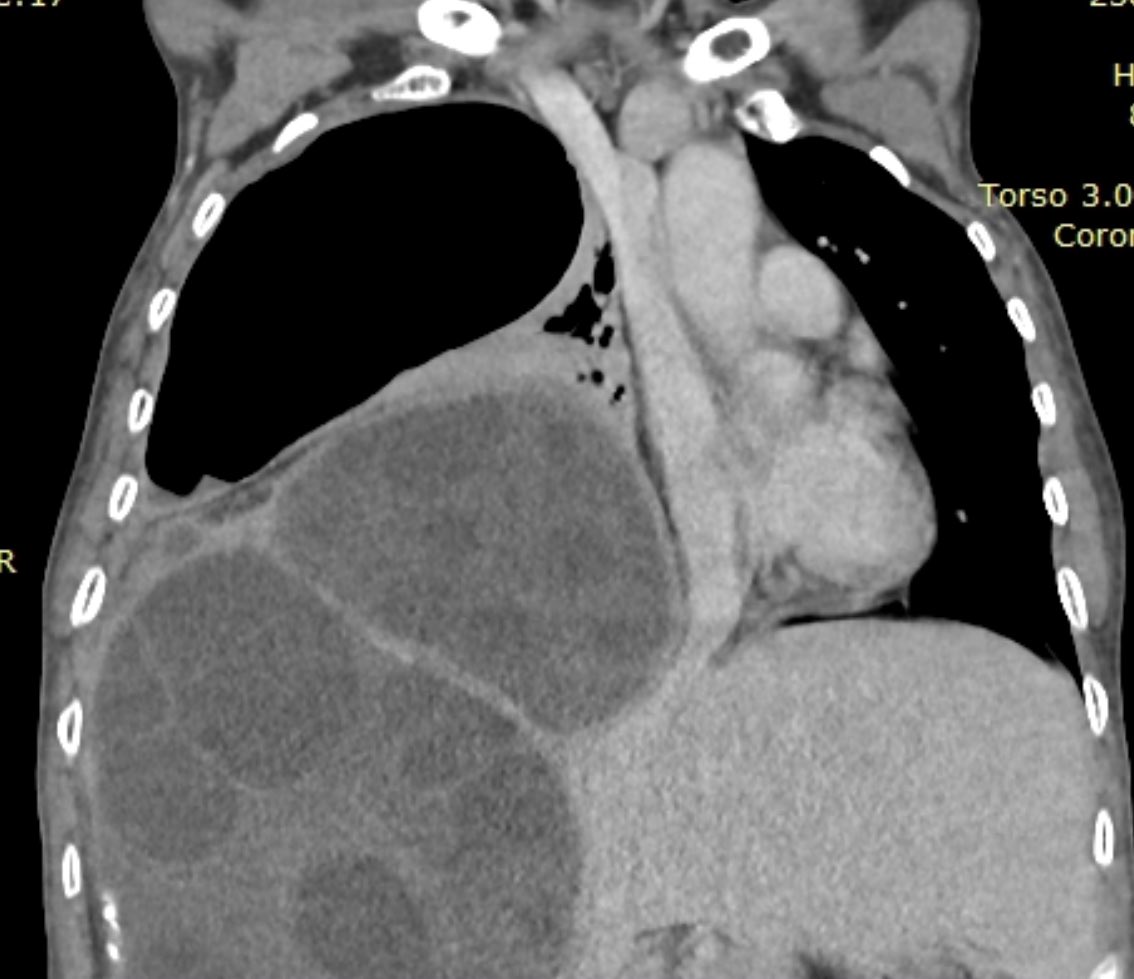

Mujer 56a , proviene de Los Andes del Perú. Acude por dolor en hipocondrio derecho y disnea desde hace 2 meses . Se sospecha de Quiste Hidatidico a nivel Pulmonar y Hepático por Ecografía . Luego se verifica con TAC #QUISTES #POCUSFIRST @ondasPOCUS @DreyfussAndrea @AngelFarro1

PAUSEHNDM2023's tweet image. Mujer 56a , proviene de Los Andes del Perú. Acude por dolor en hipocondrio derecho y disnea desde hace 2 meses . Se sospecha de Quiste Hidatidico a nivel Pulmonar y Hepático por Ecografía . Luego se verifica con TAC #QUISTES #POCUSFIRST @ondasPOCUS @DreyfussAndrea @AngelFarro1